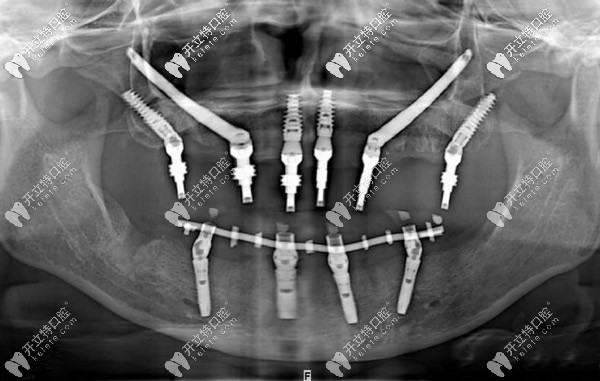

3d導(dǎo)板+all-on-6半口即刻負(fù)重,讓武漢老人當(dāng)天種植牙當(dāng)天用

即刻負(fù)重人工種植牙發(fā)布時(shí)間: 2024-11-13

多顆缺失、半口牙缺失老人如何種牙?大波圖,了解下3d導(dǎo)板即刻負(fù)重半口種植牙技術(shù),當(dāng)天種牙,當(dāng)天用。